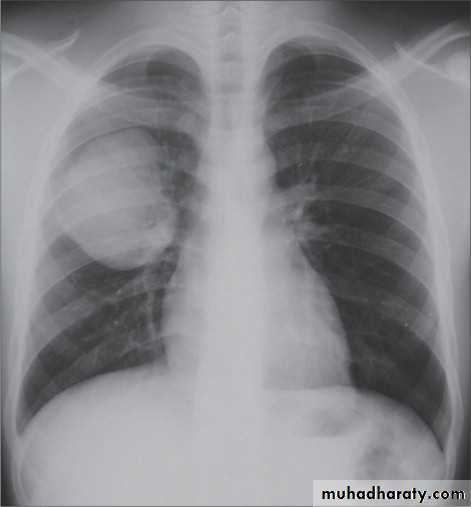

Right upper lobe collapse has distinctive features, and is usually easily identified on frontal chest radiographs .

Radiographic features

Chest radiograph

Collapse of the right upper lobe is usually relatively easy to identify on frontal radiographs. Features consist of :

increased density in the upper medial aspect of the right hemithorax

elevation of the horizontal fissure

loss of the normal right medial cardiomediastinal contour

elevation of the right hilum

hyperinflation of the right middle and lower lobe result in increased translucency of the mid and lower parts of the right lung

right juxtaphrenic peak

A common cause of lobar collapse is a hilar mass. When a right hilar mass is combined with collapse of the right upper lobe, the result is an S shape to elevated horizontal fissure. This is known as Golden S sign .

Non-specific signs indicating right sided atelectasis are also usually present including:

elevation of the hemidiaphragm

crowding of the right sided ribs

shift of the mediastinum and trachea to the right